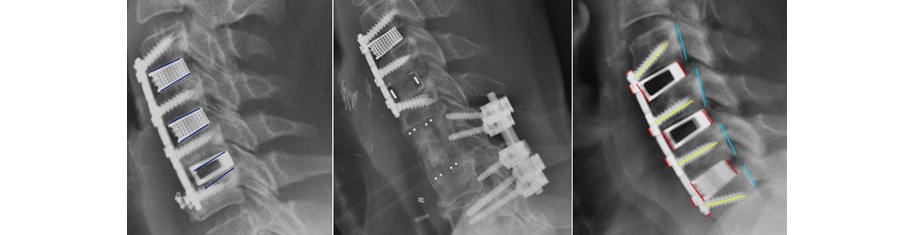

Sample radiographs from cohort

Post-operative radiographic assessment of the treated levels at each of two weeks, six weeks, six months, and twelve months revealed that the levels treated with Nexus Spine’s Tranquil® interbody devices had no measurable subsidence. In contrast, the levels treated with the other interbody devices demonstrated measurable subsidence as soon as two weeks in more than 66% of the levels treated. Subsidence is a primary indicator of spinal instability and pain. Accordingly, the results of this study suggest that Nexus Spine’s patented technology amounts to a significant improvement over the competing devices.

Peer-reviewed publications demonstrate competitive devices that exhibit at least 3 mm of subsidence in more than 52% of patients. Nexus Spine’s Tranquil® interbody cages performed much better, with no subsidence.